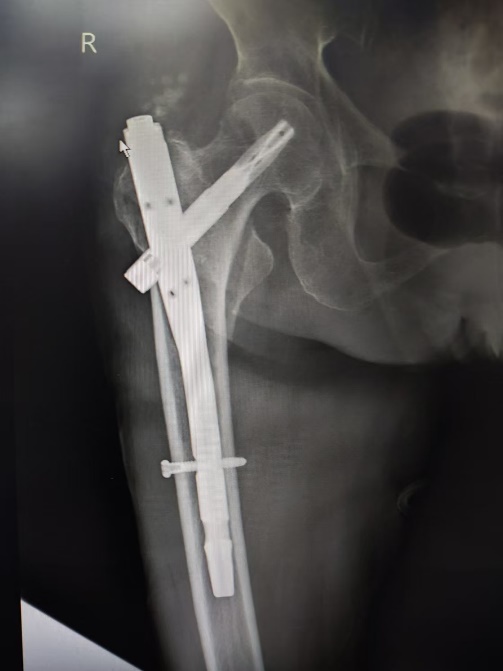

考虑患者手术的紧迫性,一旦错过手术时间窗,很难再有手术治疗机会,在多学科协作治疗下,医疗团队在患者入院第三天便为其进行了急诊手术。手术过程中,麻醉科吕建瑞主任主导,赵静医师全程保驾护航,在程斌主任指导下,薛建利副教授带领叶劲涛医师手术团队凭借其过硬的手术技艺,成功为患者实施了股骨粗隆间骨折髓内钉内固定术,骨折部位精准固定,手术损伤小,切口仅约6cm,术中出血仅约30毫升,整个手术过程流畅而高效,仅用时1小时。

平稳度过危险期后,患者转入老年内分泌科进一步调整血糖。在章琳主任医疗团队的精心治疗与悉心照料下,患者的血糖水平逐渐稳定,骨折部位愈合良好。术后一周,患者已经能够下床活动,并在家人的陪伴下进行康复训练,脸上洋溢着康复的喜悦与对生活的热爱。